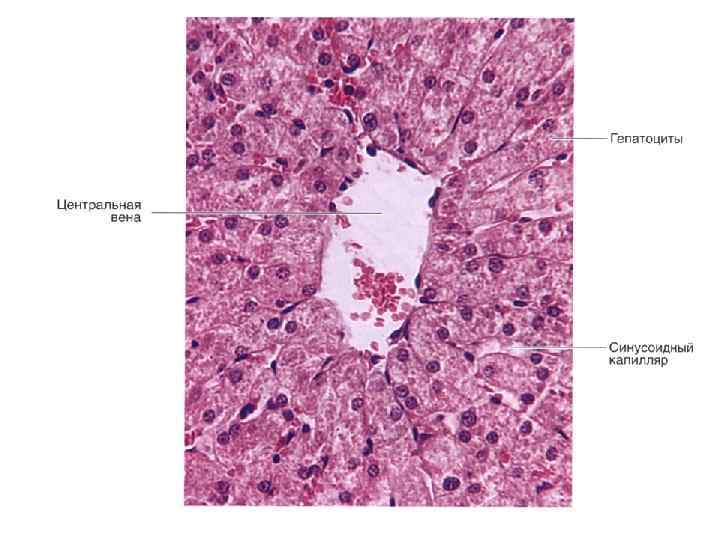

CV- центральная вена BD- желчные протоки * - синусоидные капилляры

Гликоген в гепатоцитах. Синусоиды, центральная вена

Препарат № 138 «Печень свиньи»

Препарат № 139 «Печень человека»

Препарат № 139 «Печень человека»

Препарат № 139 «Печень человека»

Центральная вена и синусоидные капилляры